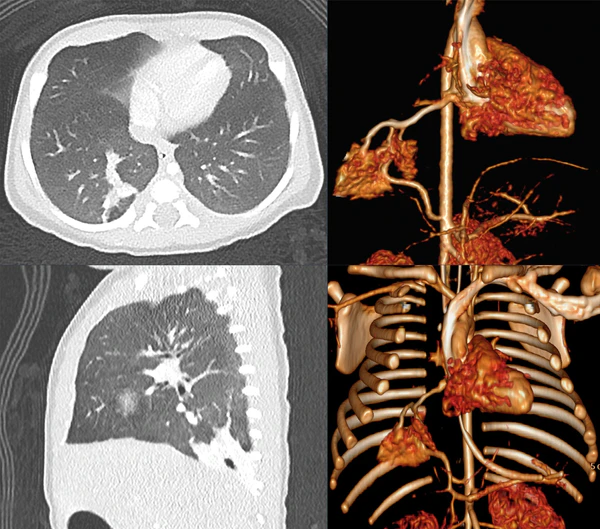

- КТ — метод выбора для диагностики ЛС, позволяет оценить не только приводящие артериальные сосуды, но и отводящие венозные, что важно для дифференциальной диагностики между интра- и экстралобарной формами секвестрации